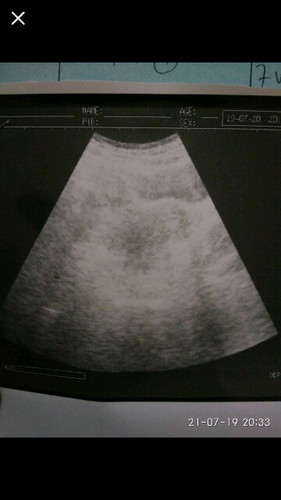

Coba bund usg ke dokter lain yg punya usg tranvagina bun biar lebih jelas klo memank sudah 7 mggu biasanya udah ada kantongnya bun contohnya seperti punya say ini bun saya usg nya usia kandungan 7 mggu bun